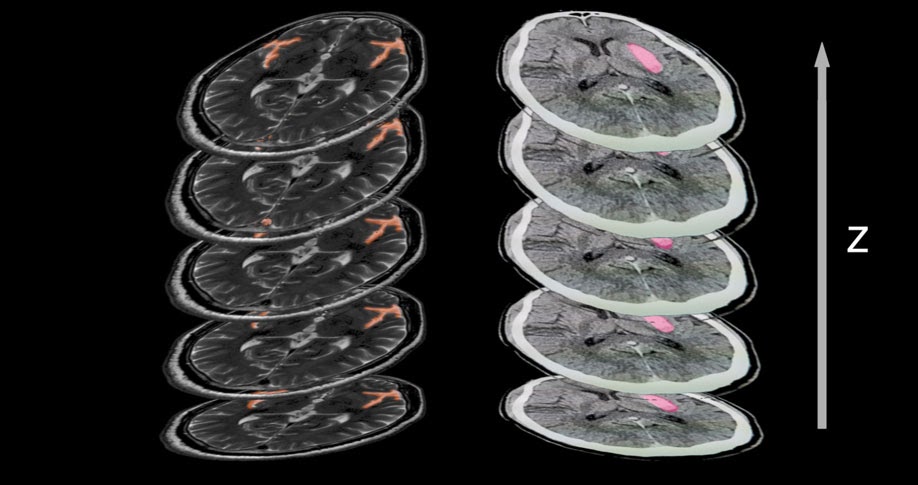

类似地,MRI、CT 或 OCT 等体积数据可以通过矢状、冠状或轴向平面浏览。

出于浏览和参考目的,这些很有用,因为它们可以更好地了解解剖结构。从机器学习的角度来看,除非您希望模型处理所有三个平面视图,否则最好坚持一个并在其他两个平面中重建这些注释。

例如,一个由 10 名注释者放射科医师组成的团队轴向标记 100 个脑 CT 病例,另一个由 10 人组成的团队在矢状面标记另外 100 个病例,将获得略有不同的结果。这些可能会给您的模型带来偏差,并导致两种平面模态的表现比团队始终将标签应用于一个系列的情况更差。

头部 CT 和 MRI 扫描的注释切片。